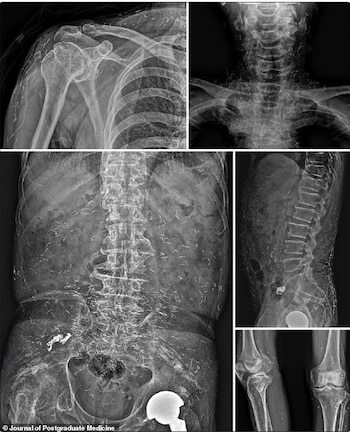

Mientras que en 2022, un hombre de 73 años ingresó por un ictus y relató haber utilizado la autoterapia con hilos de oro durante tres décadas. Las radiografías mostraron miles de estos elementos repartidos por su cuerpo. La mejoría en sus síntomas articulares se produjo solo tras recibir tratamiento médico convencional.